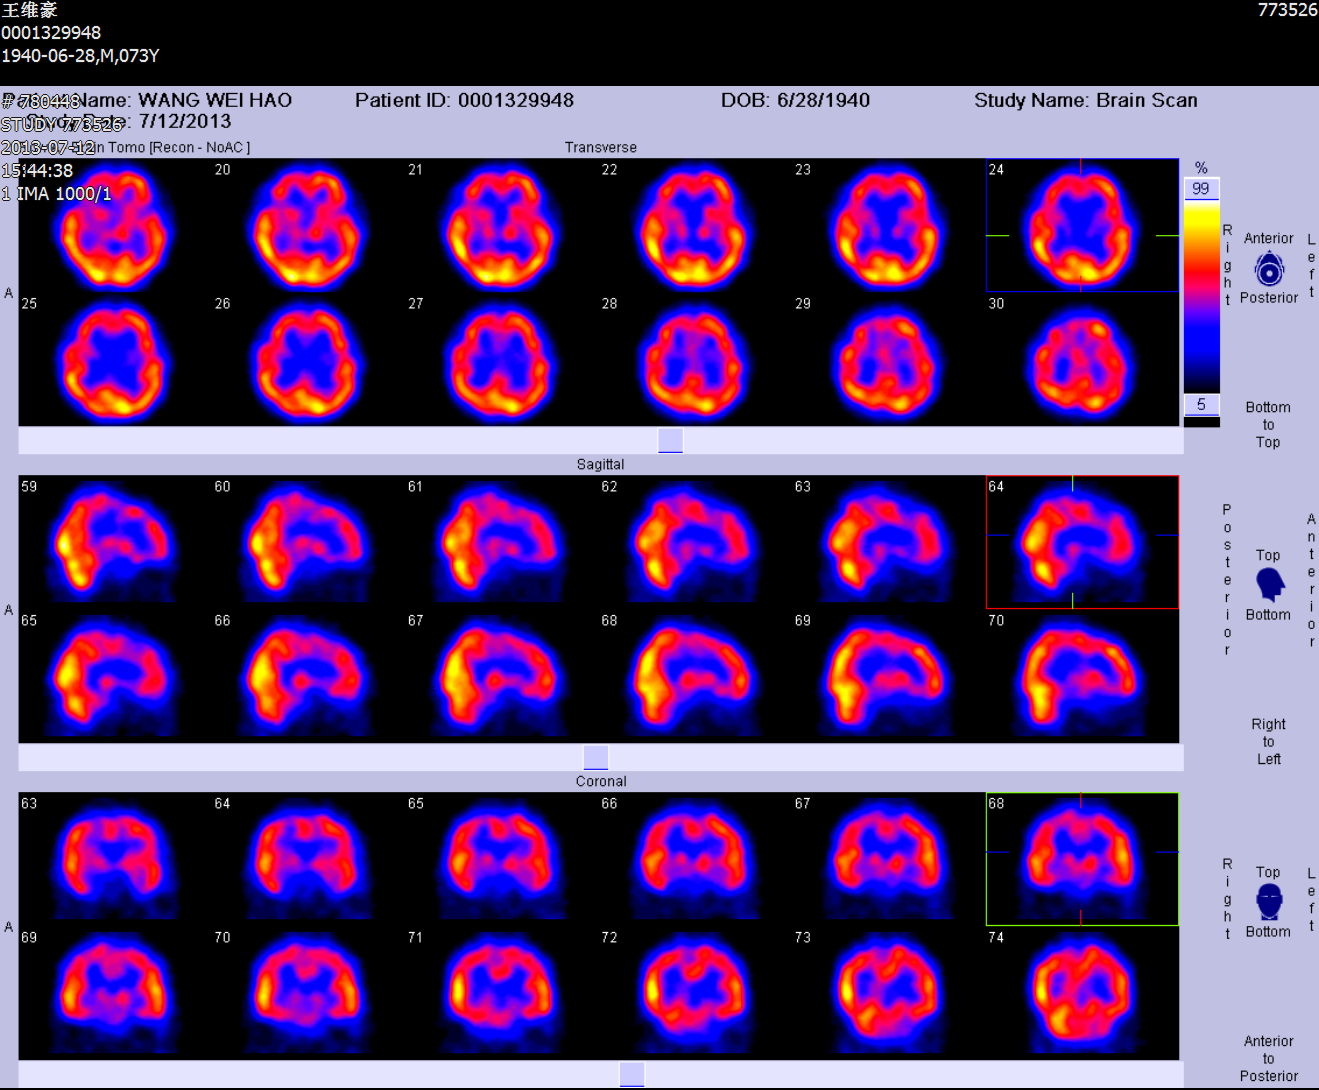

术后头颅ECT显示右侧血流灌注明显增加

术后